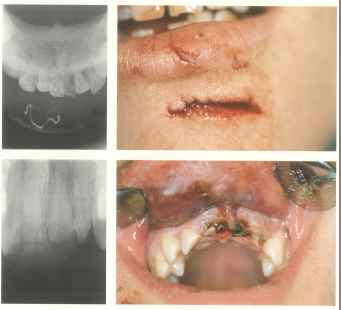

Auf dem Röntgenbild sehen wir vier verlagerte Weißheitszähne, die auf Grund ihrer Lage als Problemfälle anzusehen sind. Speziell der obere linke Weißheitszahn ist schon kariös sehr zerstört. In diesem Fall ist vor einer Langfahrt eine operative Entfernung sämtlicher Weißheitszähne durchzuführen.

Hier sind verschiedene Probleme zu sehen, die bei einer Langzeitfahrt Komplikationen erwarten lassen. Diese sollten vor der Reise abgeklärt und behoben werden. Wir gehen in unserer Praxisklinik solch einen Fall in Narkose an, sodass nach ca. 8 Tagen die Wundheilung in den meisten Fällen komplikationslos sich selbst überlassen werden kann.

Im rechten Unterkiefer liegt eine deutliche Schwellung, die durch eine Eiteransammlung in diesem Gebiet zustande kommt, ausgehend von dem Wurzelrest. Hier ist eine Inzision(Schnitt) im Notfall auch von einem angeleiteten Laien in Lokalanästhesie möglich.

Hier liegt dieselbe Situation im Oberkiefer vor, die auf ähnliche Weise anzugehen ist, wie im oberen Bild.

Ein Unfall: Zwei Verletzungen der Weichteile mit Zahntrauma. Eine solche Wunde sollte auf jeden Fall wenigstens durch Situationsnähte so versorgt werden, dass die Wundränder adaptiert sind. Sollten die Zähne frakturiert sein, müssten sie evtl. entfernt werden. Die Wundränder sind sowohl von außen wie von innen zu adaptieren. Dies kann leicht in Lokalanästhesie (leichte Technik) geschehen.